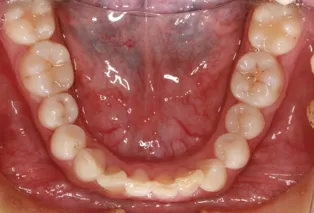

Photos intra-orales